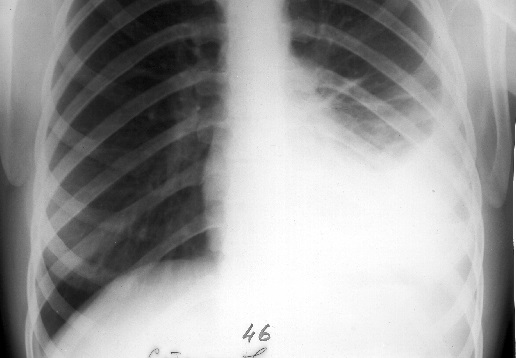

Воспаление плевры иногда способствует скоплению жидкости в плевральной впадине (плевральный выпот), что вызывает затруднение дыхания. К симптомам плеврального выпота относится лихорадка, боль в груди и сухой кашель. Плевральный выпот может возникать и без плеврита, например при сердечной недостаточности, печеночных или почечных заболеваниях.

Жидкость в плевре (плевральный выпот).